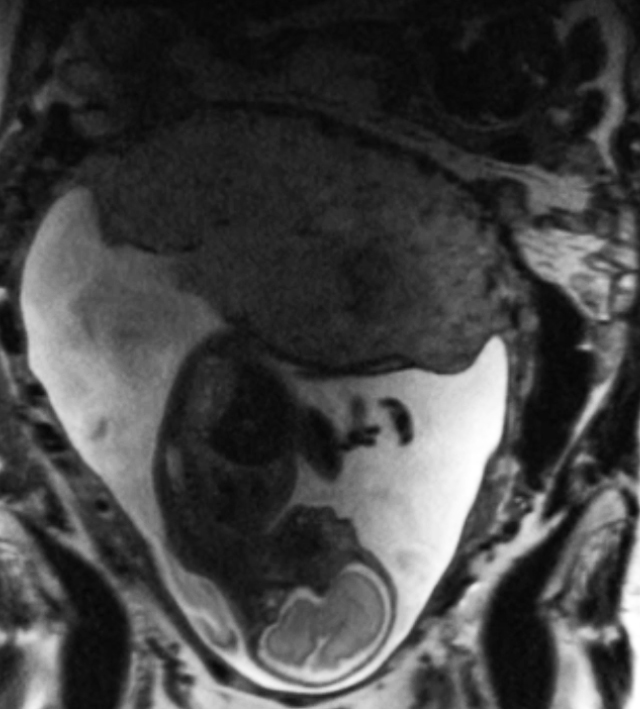

MRI of placenta and baby with the placenta highlighted in red.

A study led by OHSU researchers published in PLOS One demonstrates the potential of quantitative T2* mapping during pregnancy to identify increased risk for adverse obstetric outcome due to placental dysfunction. (OHSU)

The OHSU research team developed and validated an MRI protocol that detects a signal in the blood that is linked to oxygen content. This readout is known as T2*, and T2* values provide key information about oxygen availability and placental blood flow. Oxygen is key for fetal growth and development, so if these values deviate from the normal range, it suggests that something might be wrong. T2* values outside of the normal range could indicate an issue related to the maternal blood supply of oxygen, compromised placental transport or fetal utilization of oxygen.

The study results suggest that even data from early on in pregnancy — 10 to 20 weeks — can be effective in the identification of at-risk pregnancies. Additionally, the MRIs in the study were performed using the imaging protocol developed by the OHSU team that could be implemented on virtually all modern MRI scanners, and data analysis is quick to perform, indicating that this method may be easily adopted and expanded for use across prenatal health care settings.